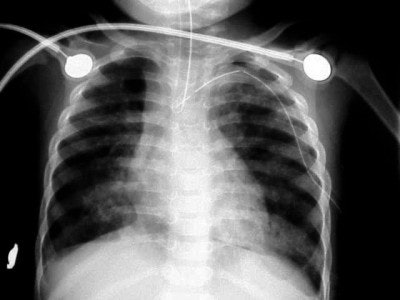

![]() |

| Figure 8 |

In figure 8, the radiographic technique has been adjusted to show lung markings after the placement of a chest tube on the left. The chest tube, however, appears to be abutting the ETT, and notice the air shadow extending around the pericardium and along the diaphragm, consistent with the diagnoses of pneumomediastinum.